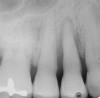

GTR, however, is still a viable option because there is consistency in published data—treating a vertical osseous lesion with this technique results in more clinical attachment gain than just open-flap debridement without performing GTR.46 The success rate in smokers, however, is significantly lower than in nonsmokers.47 Figure 11 and Figure 12] show a case in which tooth No. 22 had a large distal defect. Figure 13 shows the 6-year re-entry photograph, and Figure 14, the 6-year posttreatment radiograph, demonstrating complete clinical fill of the defect. Factors to consider in GTR include defect size (at least 3 mm to 4 mm), number of defect walls (at least two bony walls, but a three-wall defect is the most predictable to treat; Figure 15 shows a one wall defect, which is not graftable), furcation status (furcations are less predictable to obtain increased clinical attachment levels46), and mobility.48 However, patient compliance is critical in regard to both short-term and long-term success rates with GTR.

Figure 15  A one wall periodontal osseous defect.

Figure 15